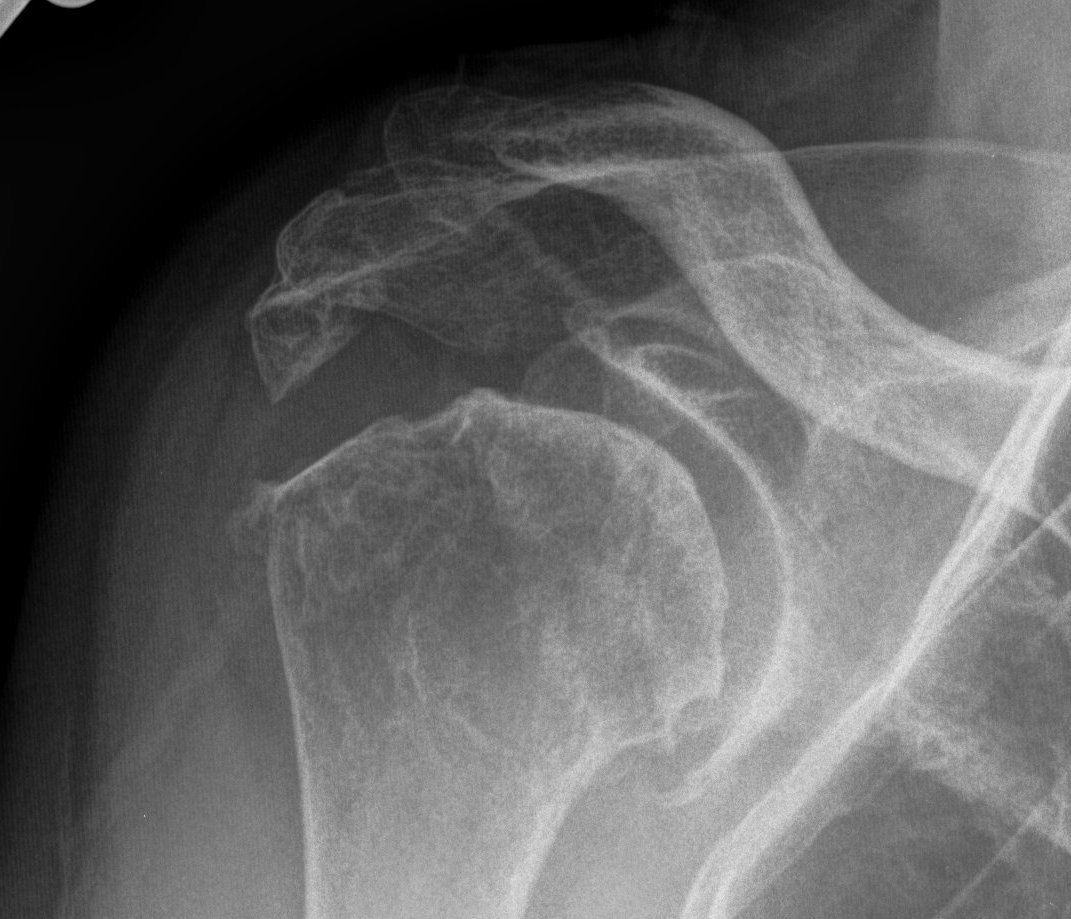

from boneschool.com

Rheumatoid Arthritis The Bone School